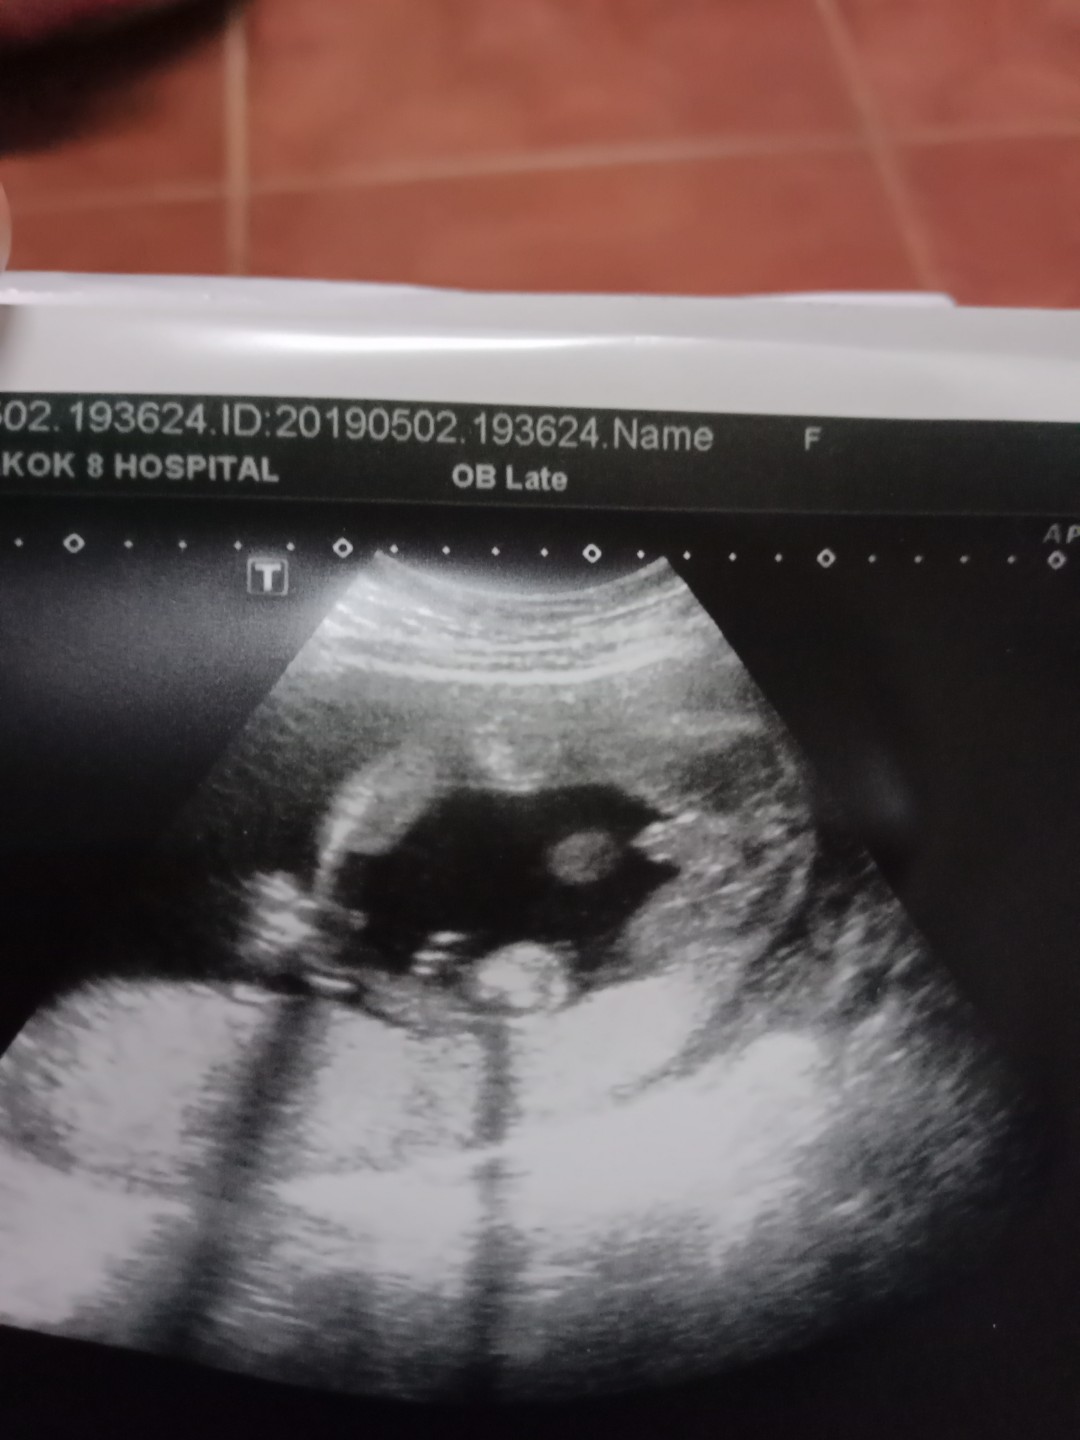

ผช ค่ะ

ผช.ค่ะ

ชายคะ